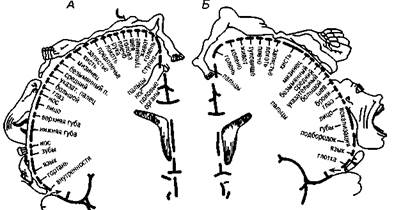

Различные участки 4-го первичного поля двигательного анализатора, построенного по соматотопическому принципу, иннервируют разные группы мышц на периферии. В 4-м поле представлена вся мышечная система человека (и поперечно-полосатая, и гладкая мускулатура). Раздражая различные участки 3-го и 4-го полей, У. Пенфилд и Г. Джаспер (1958) уточнили конфигурацию «чувствительного» и «двигательного» человечков — зон проекции и представительства различных мышечных групп (рис. 11, А, Б).

Рис. 11. Схема соматотопической проекции общей чувствительности и двигательных функций в коре головного мозга (по У. Пенфилду) :

А — корковая проекция общей чувствительности;

Б — корковая проекция двигательной системы.

Относительные размеры органов отражают ту площадь коры головного мозга,

соответствующие ощущения и движения

с которой могут быть вызваны

Как видно из рис. 11, Б, «двигательный» человечек имеет непропорционально большие губы, рот, руки, но маленькие туловище и ноги — в соответствии со степенью управляемости теми или иными группами мышц и их общим функциональным значением. «Чувствительный» человечек в целом повторяет строение «двигательного» (рис. 11, А).